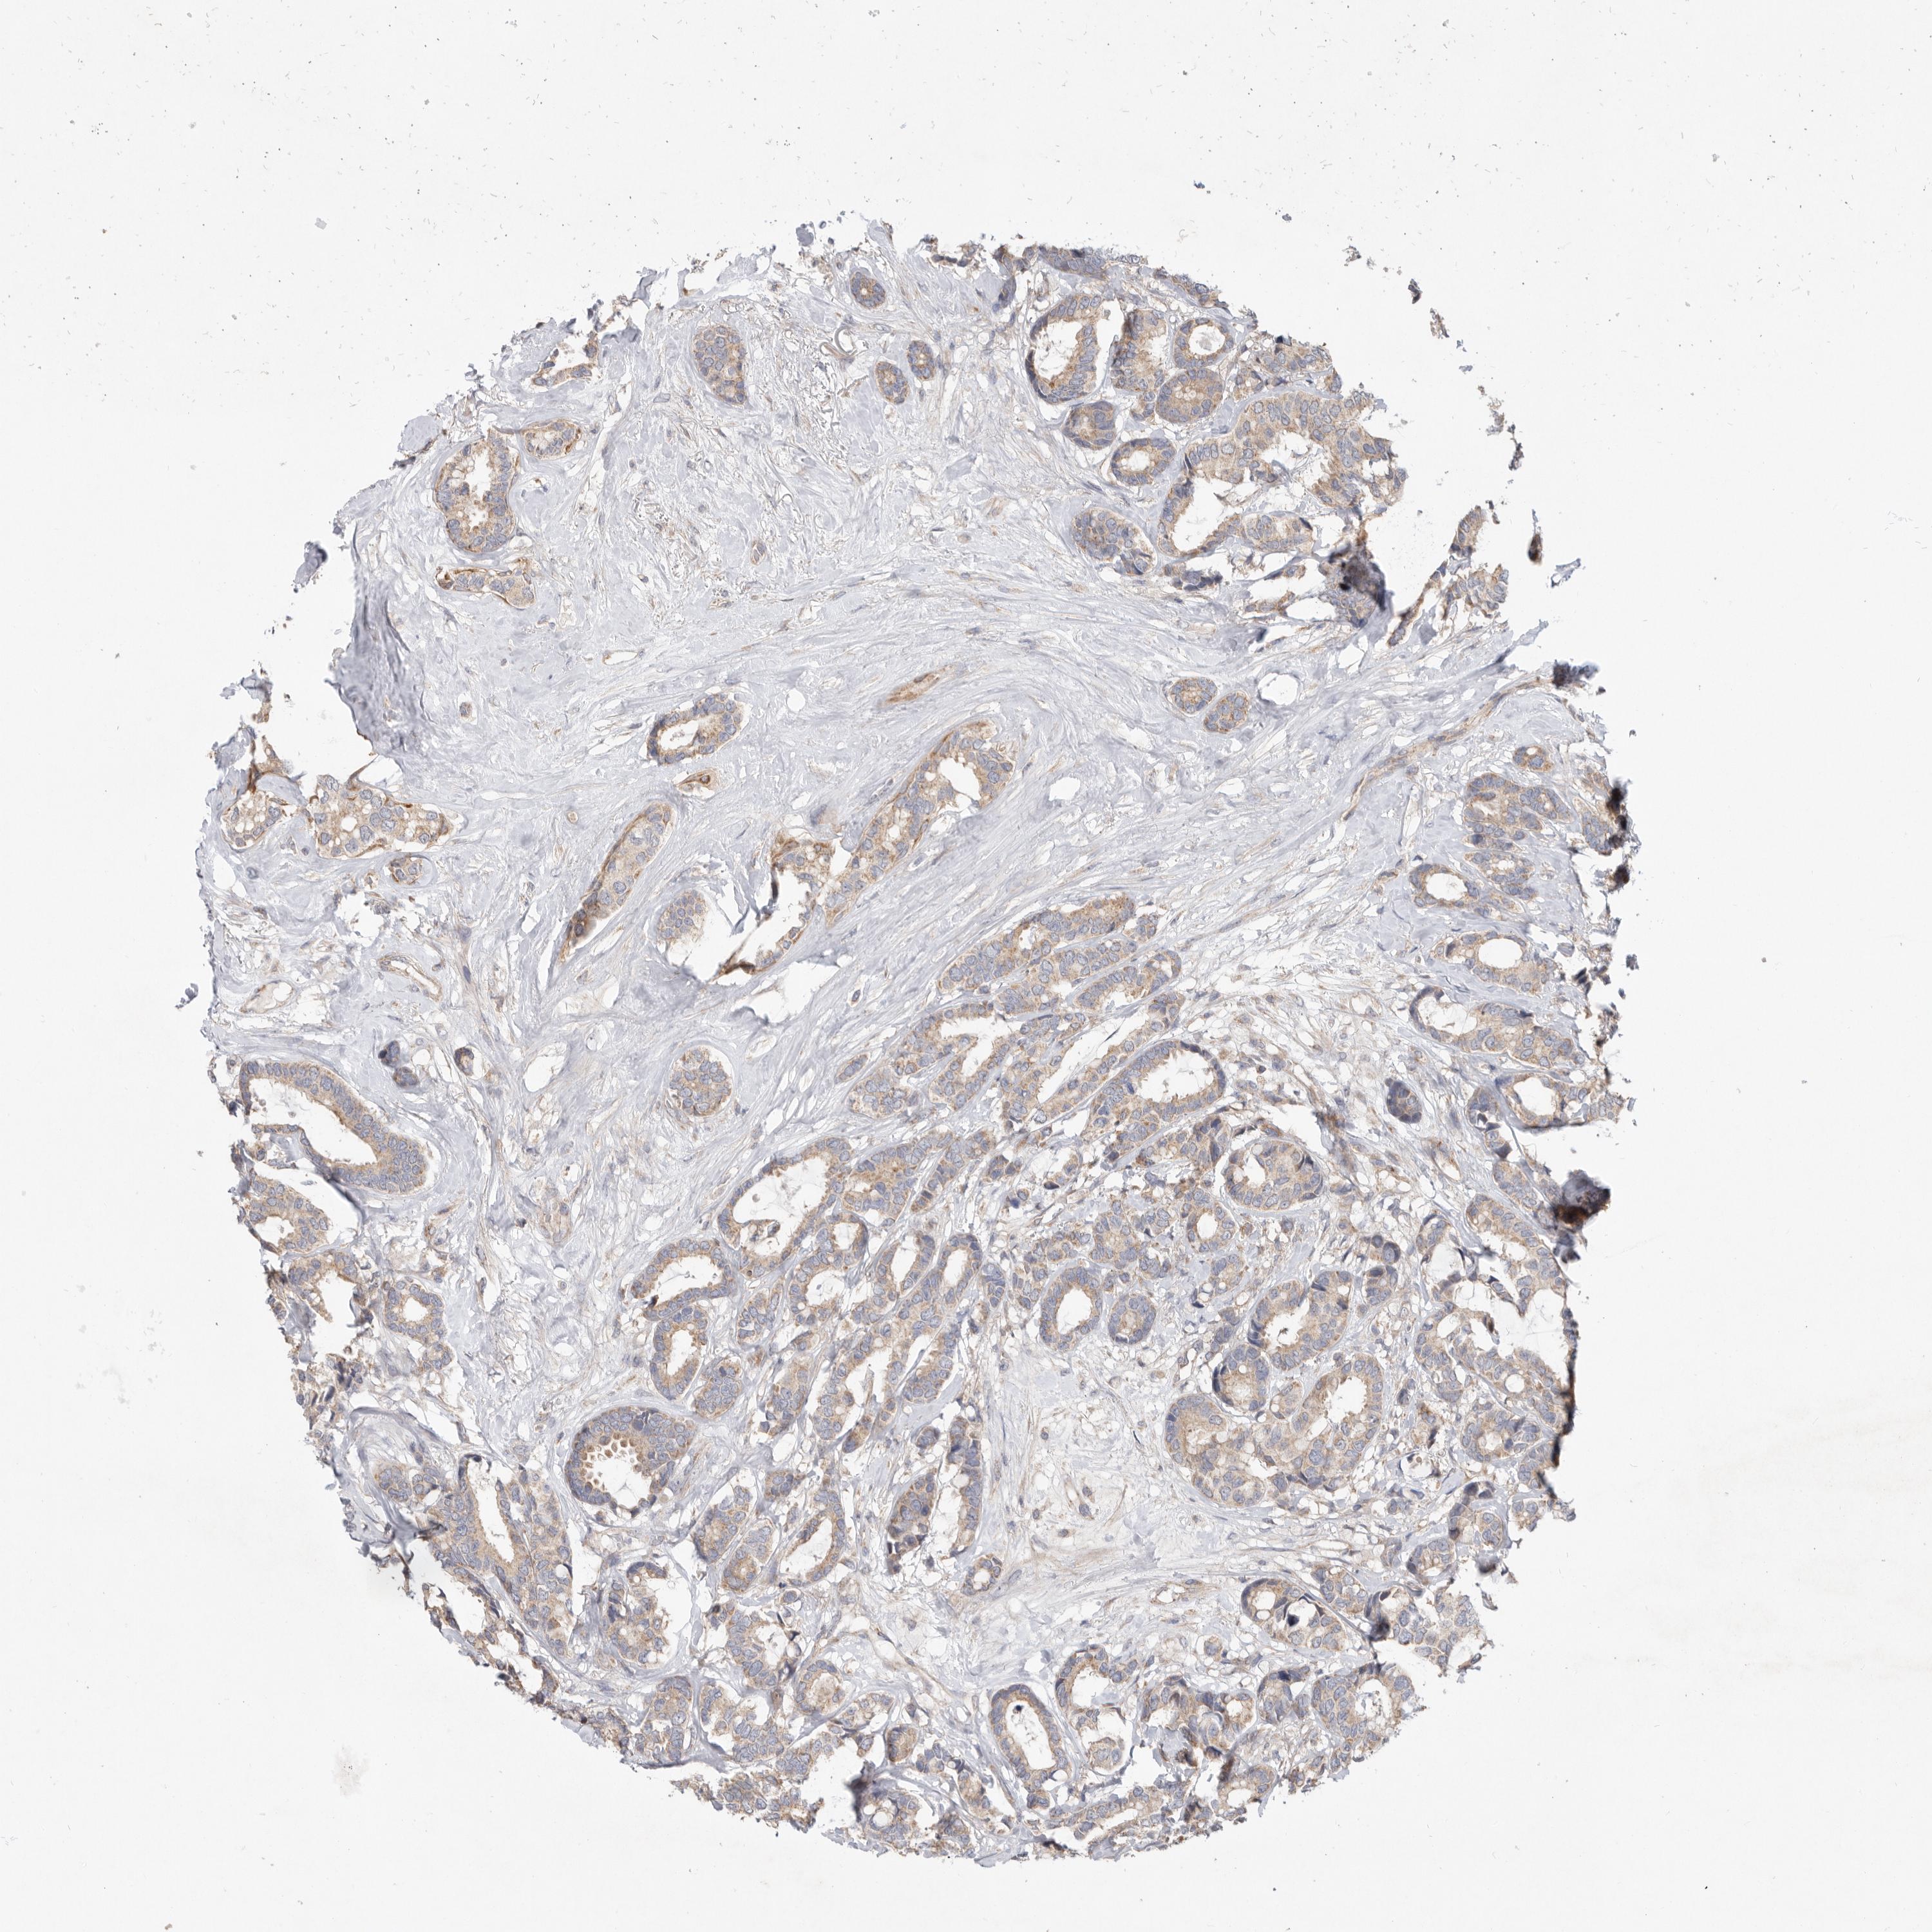

CANCER BREAST CANCER Show tissue menu

BRCA TCGA BRCA VALIDATION PROTEIN EXPRESSION